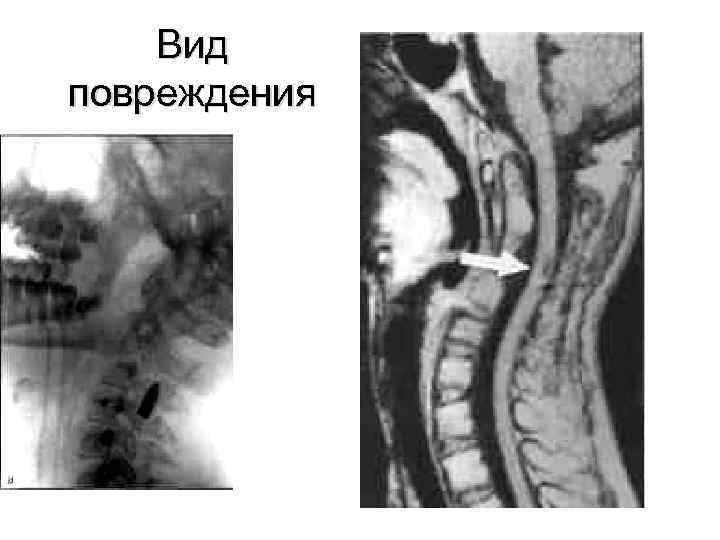

Вид повреждения